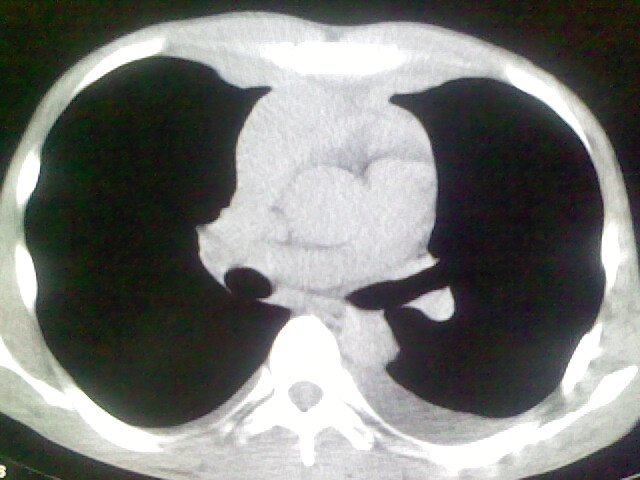

以下是引用杀毒软件在2008-9-3 6:11:00的发言:[br]侵袭性胸腺瘤------一般不侵到气管旁[br][br]考虑----纵隔淋巴瘤,心包及胸膜受累

以下是引用wzr在2008-9-3 5:30:00的发言:[br]侵袭性胸腺瘤

以下是引用随光逐影在2008-9-3 7:07:00的发言:[br]1)考虑淋巴瘤可能。2)双侧胸腔积液(以左侧为甚)。3)心包积液。